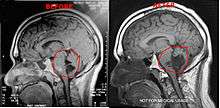

Diagnosis

Magnetic resonance imaging (MRI) and computed tomography (CT) brain scans can be used to identify these tumors.

It has been seen that a few patients have tumors that grow unusually fast, especially after surgery. After surgery it is highly suggested the patients get quarterly MRI's to monitor their tumors or as per neurosurgeons/neurologists order. If monitoring the tumor, it is suggested to use the same facility for each scan. Using different facilities can result in minor variations in the scan which can result in false measurements of the brain tumor.